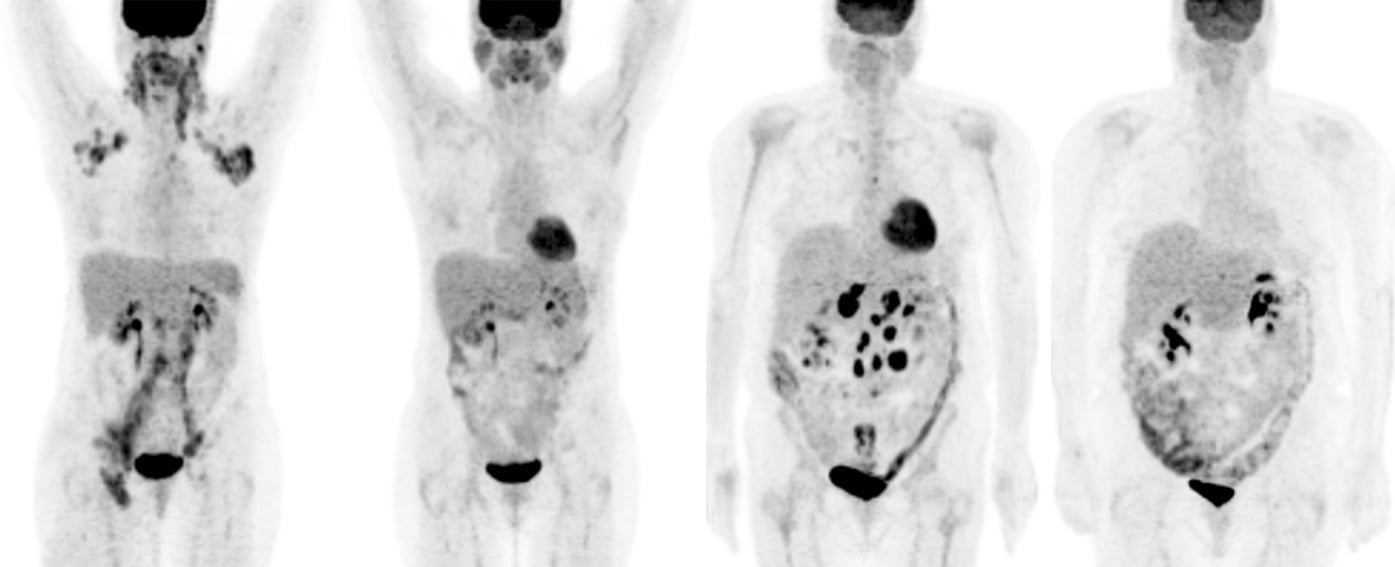

期間限定特別価格 Roentgen Signs 9780721663029 Abdomen: Imaging: Diagnostic in 医学一般の詳細情報

Roentgen Signs in Diagnostic Imaging: Abdomen: 9780721663029。PET Scans Guiding Chemo Boost Remission for Hodgkin Patients。Roentgen Signs in Diagnostic Imaging: The Chest。期間限定割引SW.13 特级黄小米 小米 あわ 粟 健康食糧 粗糧 40038y。 閉じる